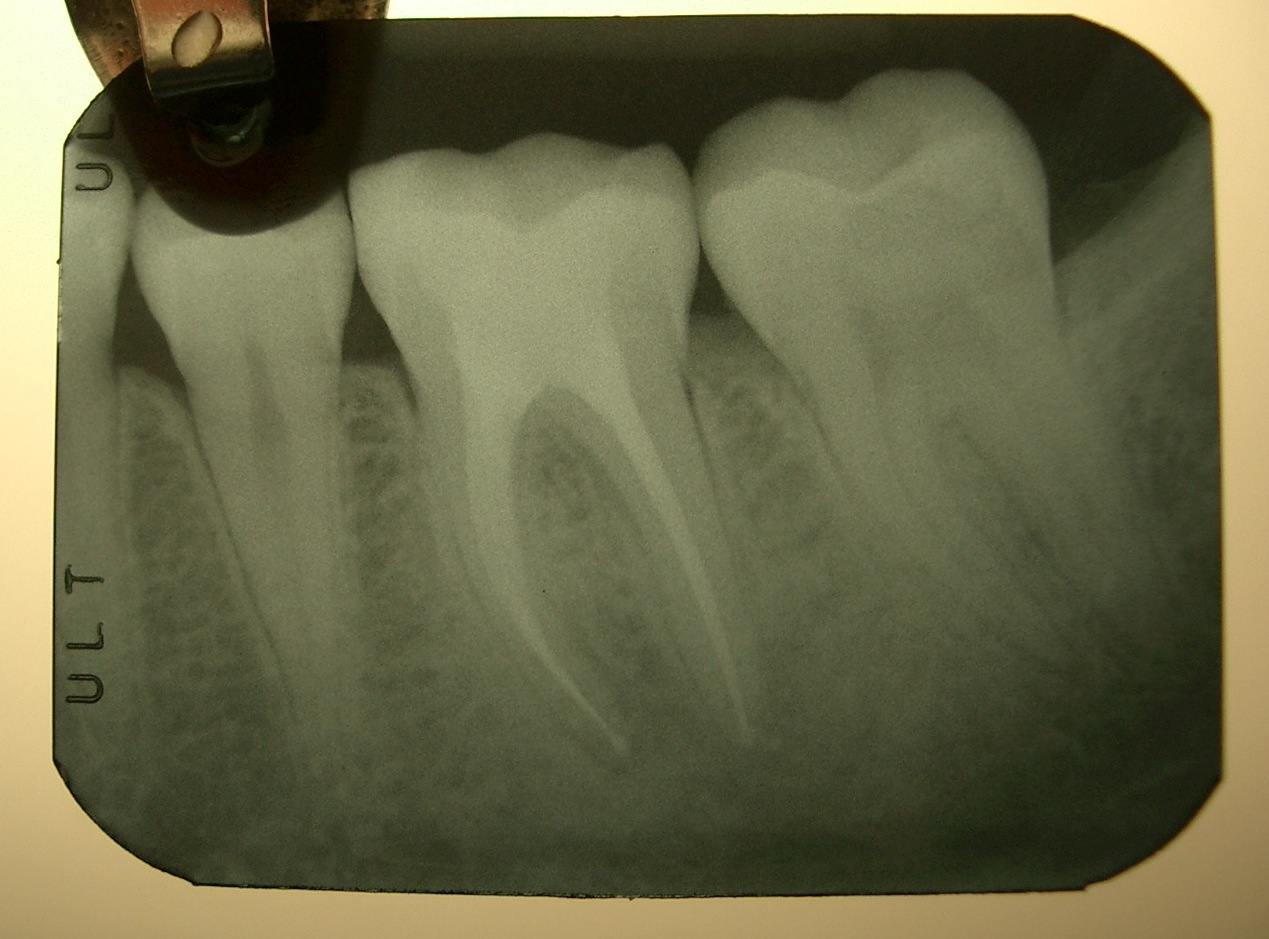

Paziente di 16 anni, con lesione apicale al 36 scoperta durante l'esecuzione di un controllo semestrale. L'elemento presentava un restauro in amalgama non particolarmente esteso, ma era negativo a tutti i test di vitalità.

Le RX mostrano la terapia canalare appena eseguita, e la RX controllo a 3 mesi, per valutare la guarigione della lesione apicale estesa.